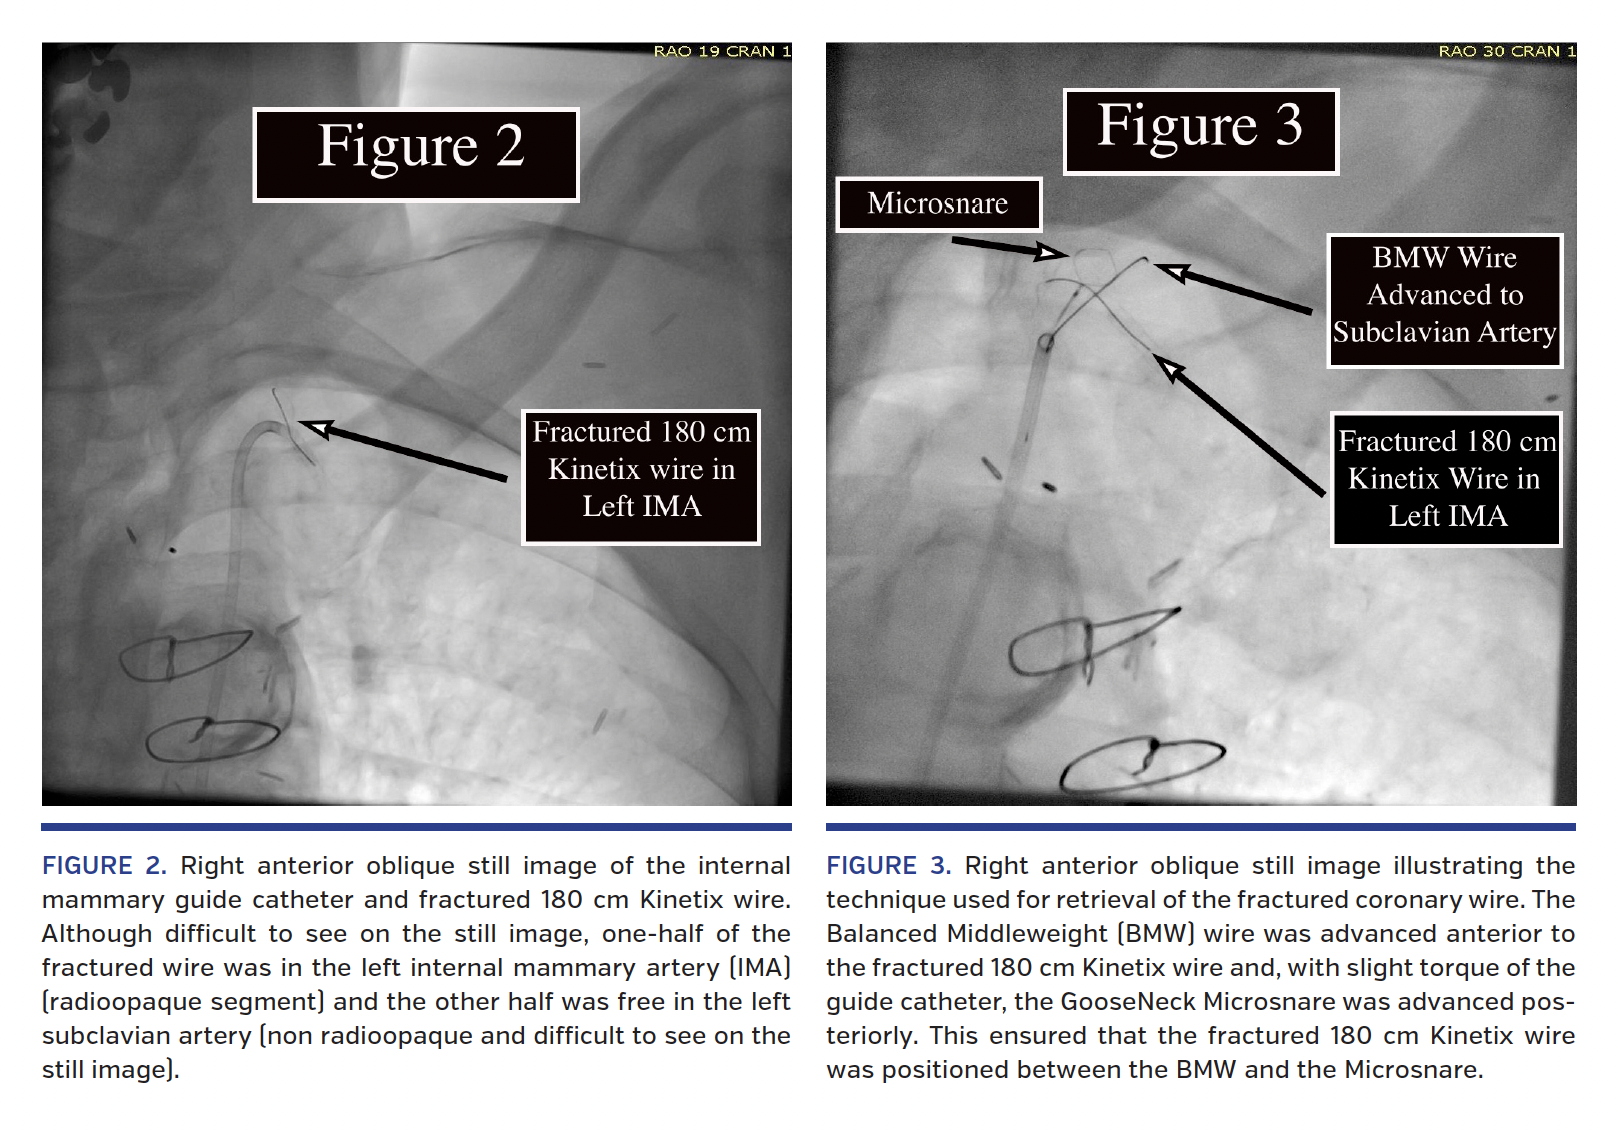

An 84-year-old man had a history of two prior coronary artery bypass graft operations, multiple percutaneous coronary interventions, and left ventricular systolic dysfunction. He presented with recurrent angina, Canadian Cardiovascular Society angina class III. Coronary angiography revealed severe three-vessel coronary disease and bypass graft angiography revealed a totally occluded stent in the proximal left internal mammary artery (LIMA) (Figure 1). As such, percutaneous LIMA intervention was planned. A 180 cm Kinetix wire (Boston Scientific) was advanced into the occluded LIMA via a 6 Fr LIMA guide catheter. The tip of the wire became entrapped in the stented segment of the occluded vessel. Further manipulation resulted in wire fracture. The body of the wire was removed while approximately 20 centimeters of the soft tip remained in the patient, with half in the LIMA and the other half free in the left subclavian artery (Figure 2). Traditional retrieval techniques were unsuccessful. A novel retrieval technique was attempted. A Balance Middleweight universal coronary wire (Abbott Vascular) was advanced anterior and distal to the fractured wire. The guide catheter was torqued posteriorly, and an Amplatz GooseNeck Microsnare (Covidien) was advanced into the mid subclavian artery also distal to the fractured wire. The shaft of the Balance Middleweight wire, rather than the soft tip, was snared distal to the fractured wire. As the Microsnare and snared Balance Middleweight wire were pulled back, the Kinetix wire that had been positioned between the two devices was securely trapped and successfully removed from the patient (Video 1). Although fractured coronary wires are a rare occurrence, failures to retrieve them successfully put patients at undue risk.1 This technique can be used when traditional retrieval with a Microsnare system is unsuccessful.